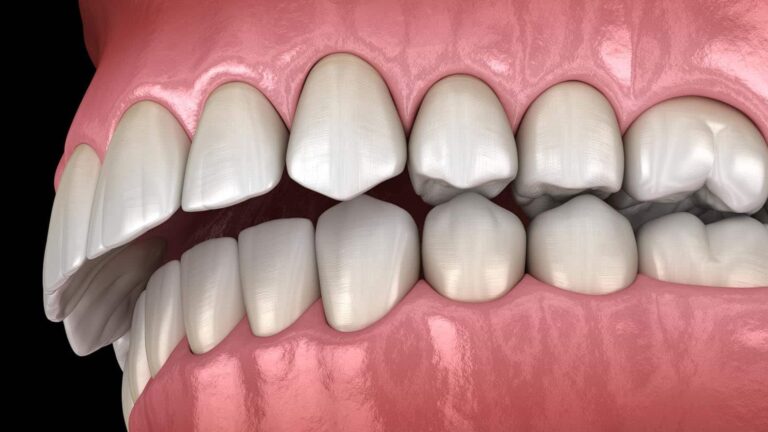

Definicja i znaczenie Aparat retencyjny to specjalistyczne urządzenie stomatologiczne, które stosuje się po zakończeniu leczenia ortodontycznego, ponieważ jego głównym zadaniem jest nie tylko utrzymanie prawidłowego ustawienia zębów, ale także zapobieganie nawrotowi wady zgryzu. W klinice stomatologicznej ortodonta Wrocław dobiera odpowiedni…